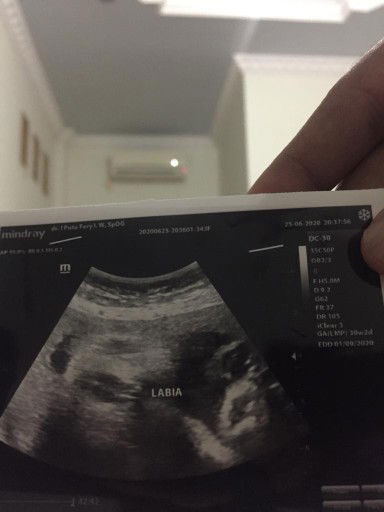

usg

Ini cowok/cewek ? Kata dokter cewek...tpi, yg di lihat mana nya ?